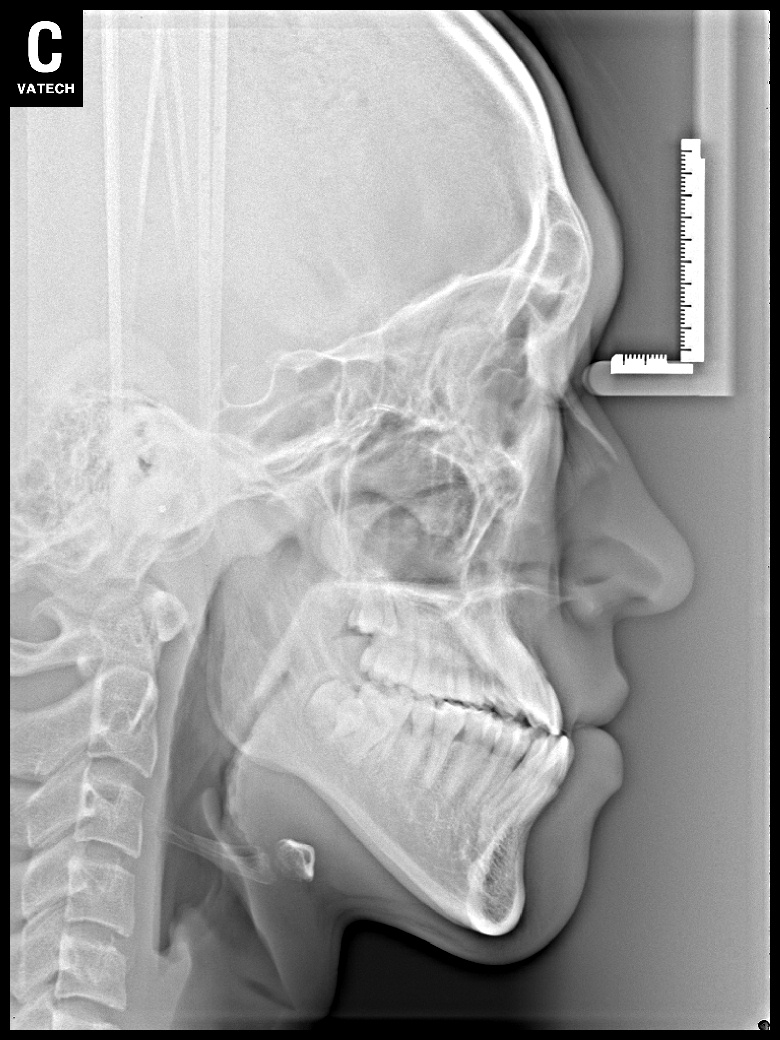

치료 전 사진입니다.